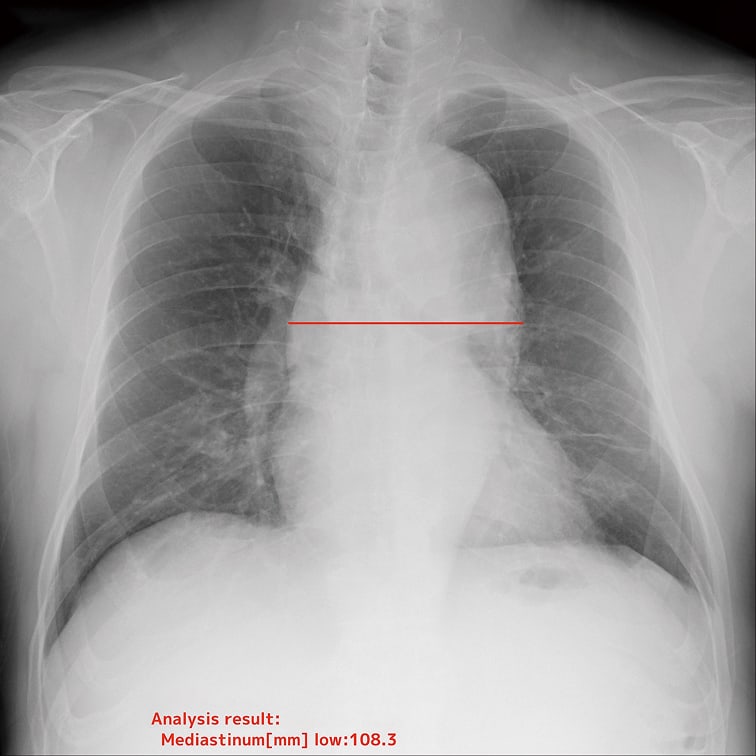

- 縦隔幅(上部、中部、下部)

EIRLが胸部X線画像上のランドマークを認識し、自動で計測。計測のばらつきを抑えながら、日常業務の負担を大幅に軽減します。

自動計測機能